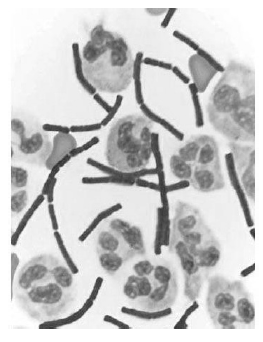

A figura precedente mostra o fluido cérebro-espinhal de um paciente com infecção bacteriana. Considerando essa informação e os múltiplos aspectos a ela relacionados, julgue o item a seguir.

De acordo com a figura, o fluido cérebro-espinhal desse paciente contém acúmulo de células imunológicas mononucleares.

Bactérias que têm a mesma forma das apresentadas nessa figura podem ser transmitidas por inalação, ingestão ou por via cutânea.